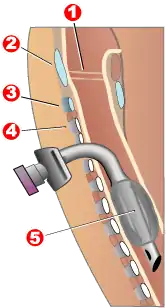

Modern "volume ventilators/respirators," which deliver an adjustable volume (amount) of air to the person with each breath, are valuable in the treatment of people with muscular dystrophy-related respiratory problems. The ventilator may require an invasive endotracheal or tracheotomy tube through which air is directly delivered, but for some people, noninvasive delivery through a face mask or mouthpiece is sufficient. Positive airway pressure machines, particularly bilevel ones, are sometimes used in this latter way. The respiratory equipment may easily fit on a ventilator tray on the bottom or back of a power wheelchair with an external battery for portability.

Ventilator treatment may start in the mid- to late teens when the respiratory muscles can begin to collapse. If the vital capacity has dropped below 40% of normal, a volume ventilator/respirator may be used during sleeping hours, a time when the person is most likely to be underventilating (hypoventilating). Hypoventilation during sleep is determined by a thorough history of sleep disorder with an oximetry study and a capillary blood gas (see pulmonary function testing).

A cough assist device can help with excess mucus in lungs by hyperinflation of the lungs with positive air pressure, then negative pressure to get the mucus up. If the vital capacity continues to decline to less than 30 percent of normal, a volume ventilator/respirator may also be needed during the day for more assistance. The person gradually will increase the amount of time using the ventilator/respirator during the day as needed. However, there are also people with the disease in their 20s who have no need for a ventilator.